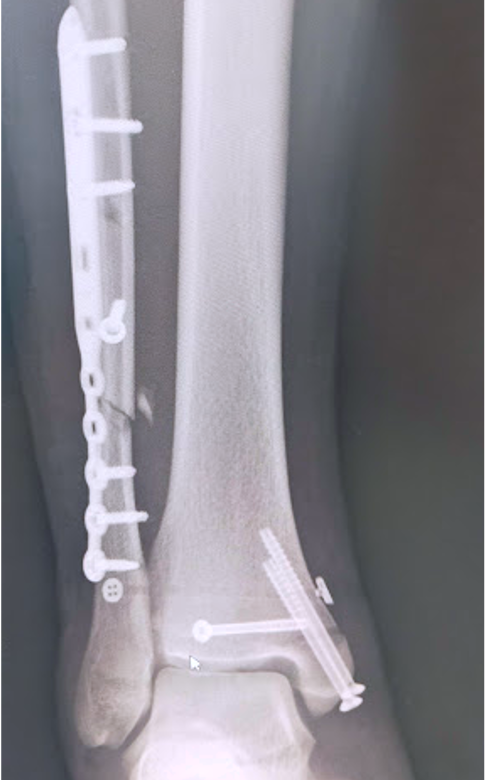

ひざ、股関節を含む、四肢の骨折に対しては、適応があれば手術加療を行い、機能改善および早期の社会復帰を目指しています。

関節を含む骨折は、機能障害を起こしやすく、正確に関節を再建する必要があり、早期リハビリ、機能改善にはとても重要です。

その他、上肢の骨折、足関節や下腿骨などの下肢骨折など、日常的に発生することの多いほとんどの骨折に対する治療に対応しています。

足関節脱臼骨折に対する骨接合術